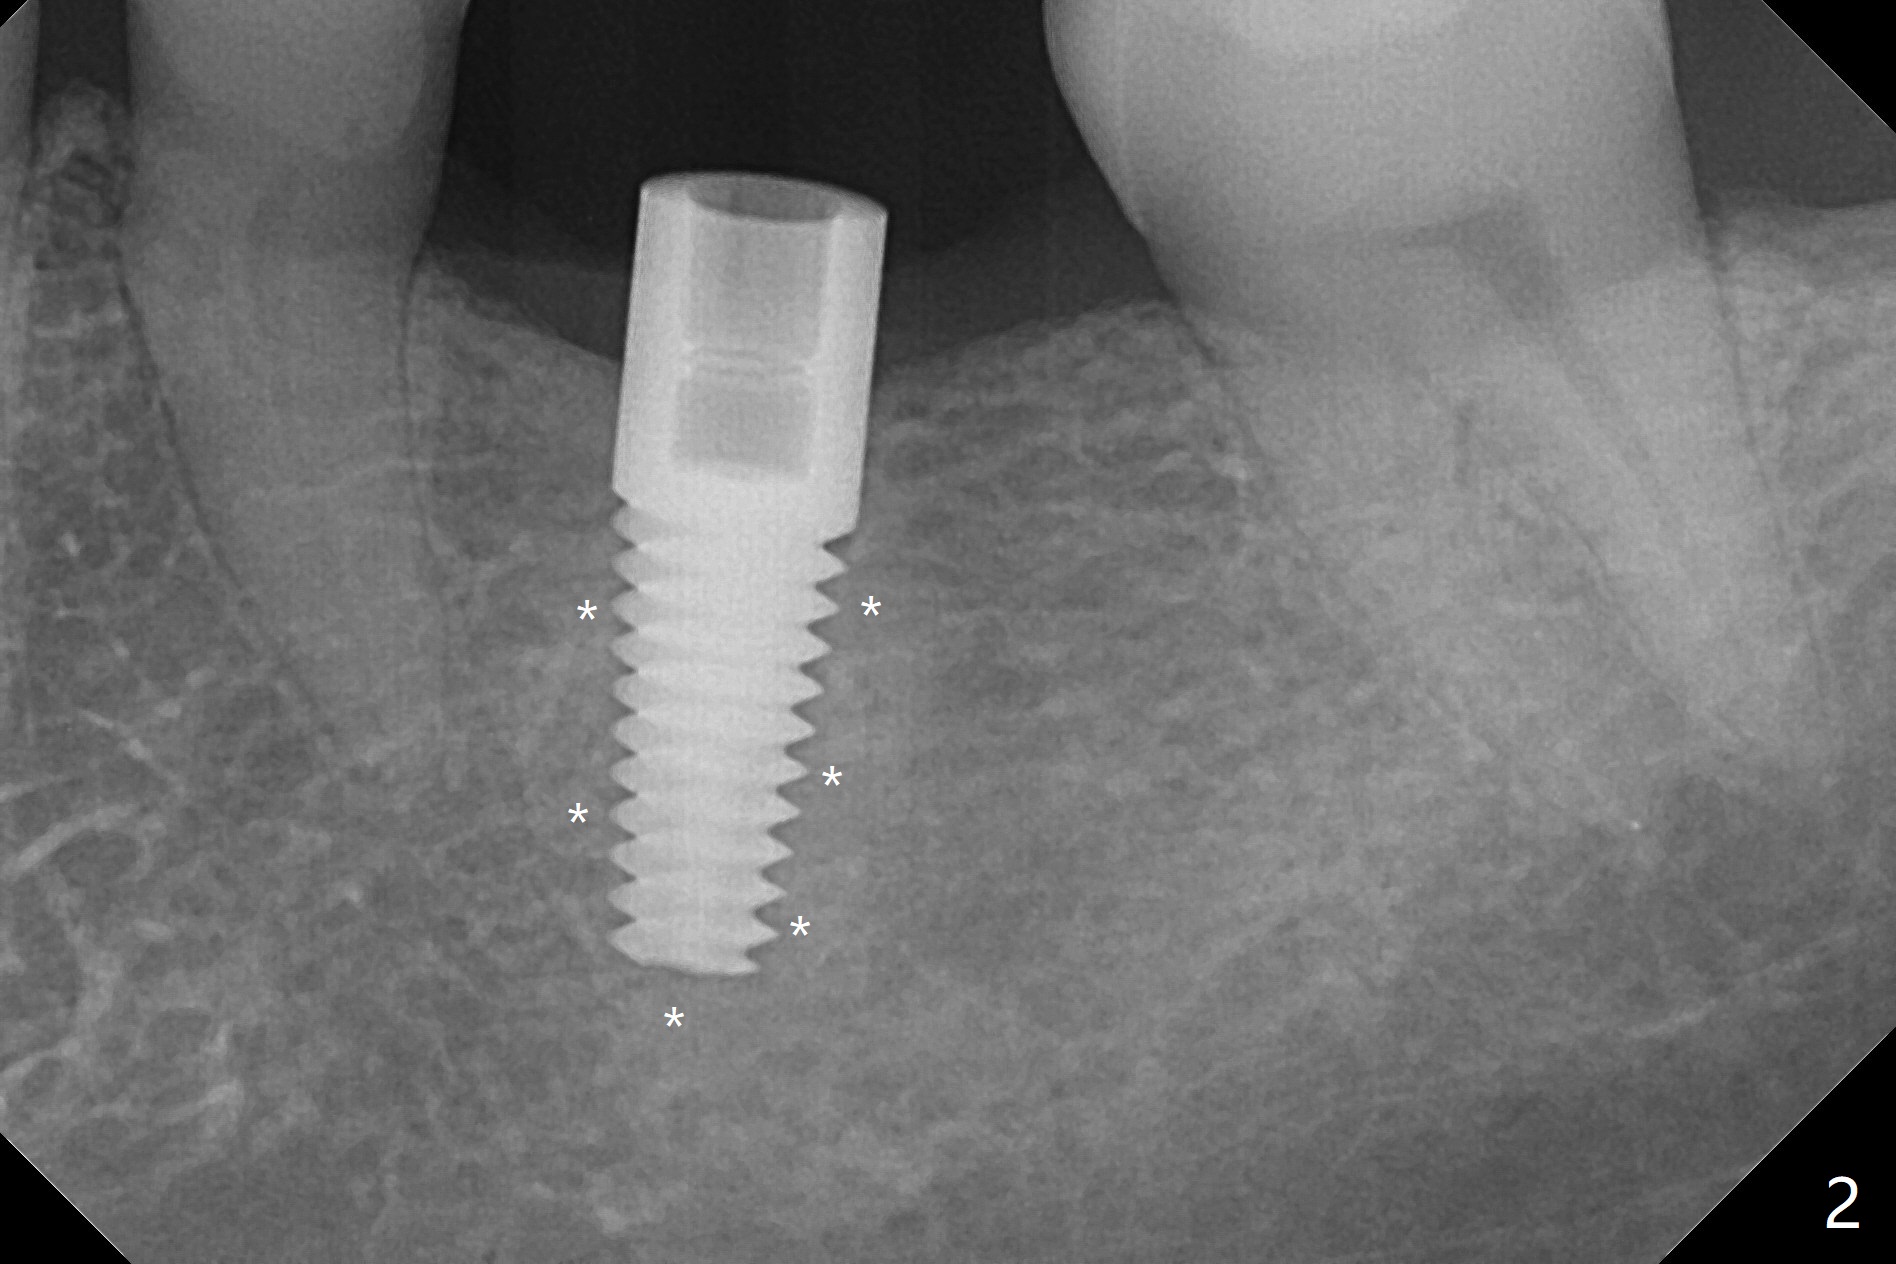

After 4.0x10 mm drill with 9 mm offset for 4.5x10 mm bone-level implant at #19, a 4.5x17 mm tissue level tap is inserted with apparently low torque (probably without reaching the depth). When a 4.5x14 mm tissue level implant is placed with high torque, a 4.5x7.3 mm drill is used for ~ 6.5 mm. The implant loses the primary stability with over-insertion (Fig.1). When an abutment is placed, the implant is critically loose. Mixture of autogenous bone, Osteogen and allograft is placed in the osteotomy. The implant regains stability with better placement level for restoration (Fig.2). In fact the bone density around the implant increases (Fig.2 *). For the first 7 days postop, the patient has to take Advil. When he returns for follow up 8 days postop (Fig.3), the pain decreases, while there is minor degree of lower lip paresthesia. Medrol Dose Pak and Tylenol III are prescribed. The implant is loose 24 days postop; after removal of the implant and apparently infected bone graft, a 7x14 mm dummy implant is inserted with <20 Ncm and 3-4 mm clearance (Fig.4). A longer dummy implant seems to improve stability (Fig.5). So does the definitive implant (Fig.6,7, 25 Ncm), but it is placed low. The gingiva looks healthy 13 days postop (2nd placement). A healing cap will be placed for restoration ~ 3 months postop. CT will be taken if the implant needs to be backed up to determine whether there is enough bone buccolingually. Due to coronavirus and prolonged placement of a healing abutment with poor oral hygiene, the buccal gingiva of the implant is erythematous 1 year postop (Fig.8 healing cap just removed) with bone loss (Fig.9,10 *). Sticky bone seems to be necessary. A 6x5 mm abutment with slots will be placed to hold periodontal dressing in place.